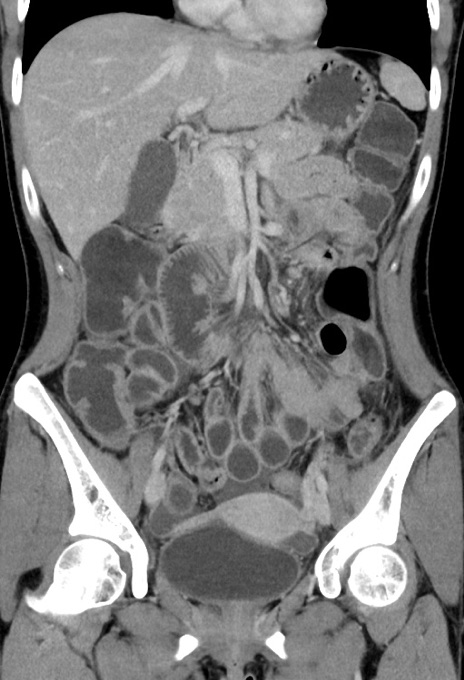

症例17(冠状断像)

【症例】20歳代女性

【主訴】嘔吐、下腹部痛

【現病歴】昨日夕食後に嘔吐し下腹部痛が出現。本日になっても嘔吐持続し改善しないため来院。

【身体所見】意識清明、BT 37.2℃、BP 108/67mmHg、腹部:平坦、やや硬、下腹部正中から右にかけて圧痛あり、反跳痛軽度あり、tapping pain(+)。

【データ】WBC 13600、CRP 14.94